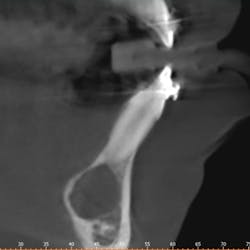

Clinically, there was no buccal or lingual expansion (figure 1). The patient’s medical history was noncontributory. A CT scan revealed a 1.5 cm x 1 cm well-defined, circular, hypodense area inferior to the lower incisors (figures 2–4).

The radiographic appearance of a simple bone cyst can mimic many other odontogenic and nonodontogenic radiolucent lesions. Sometimes there is visible scalloping around teeth roots, and though usually unilocular with well-defined borders, these lesions can be multilocular with irregular borders.